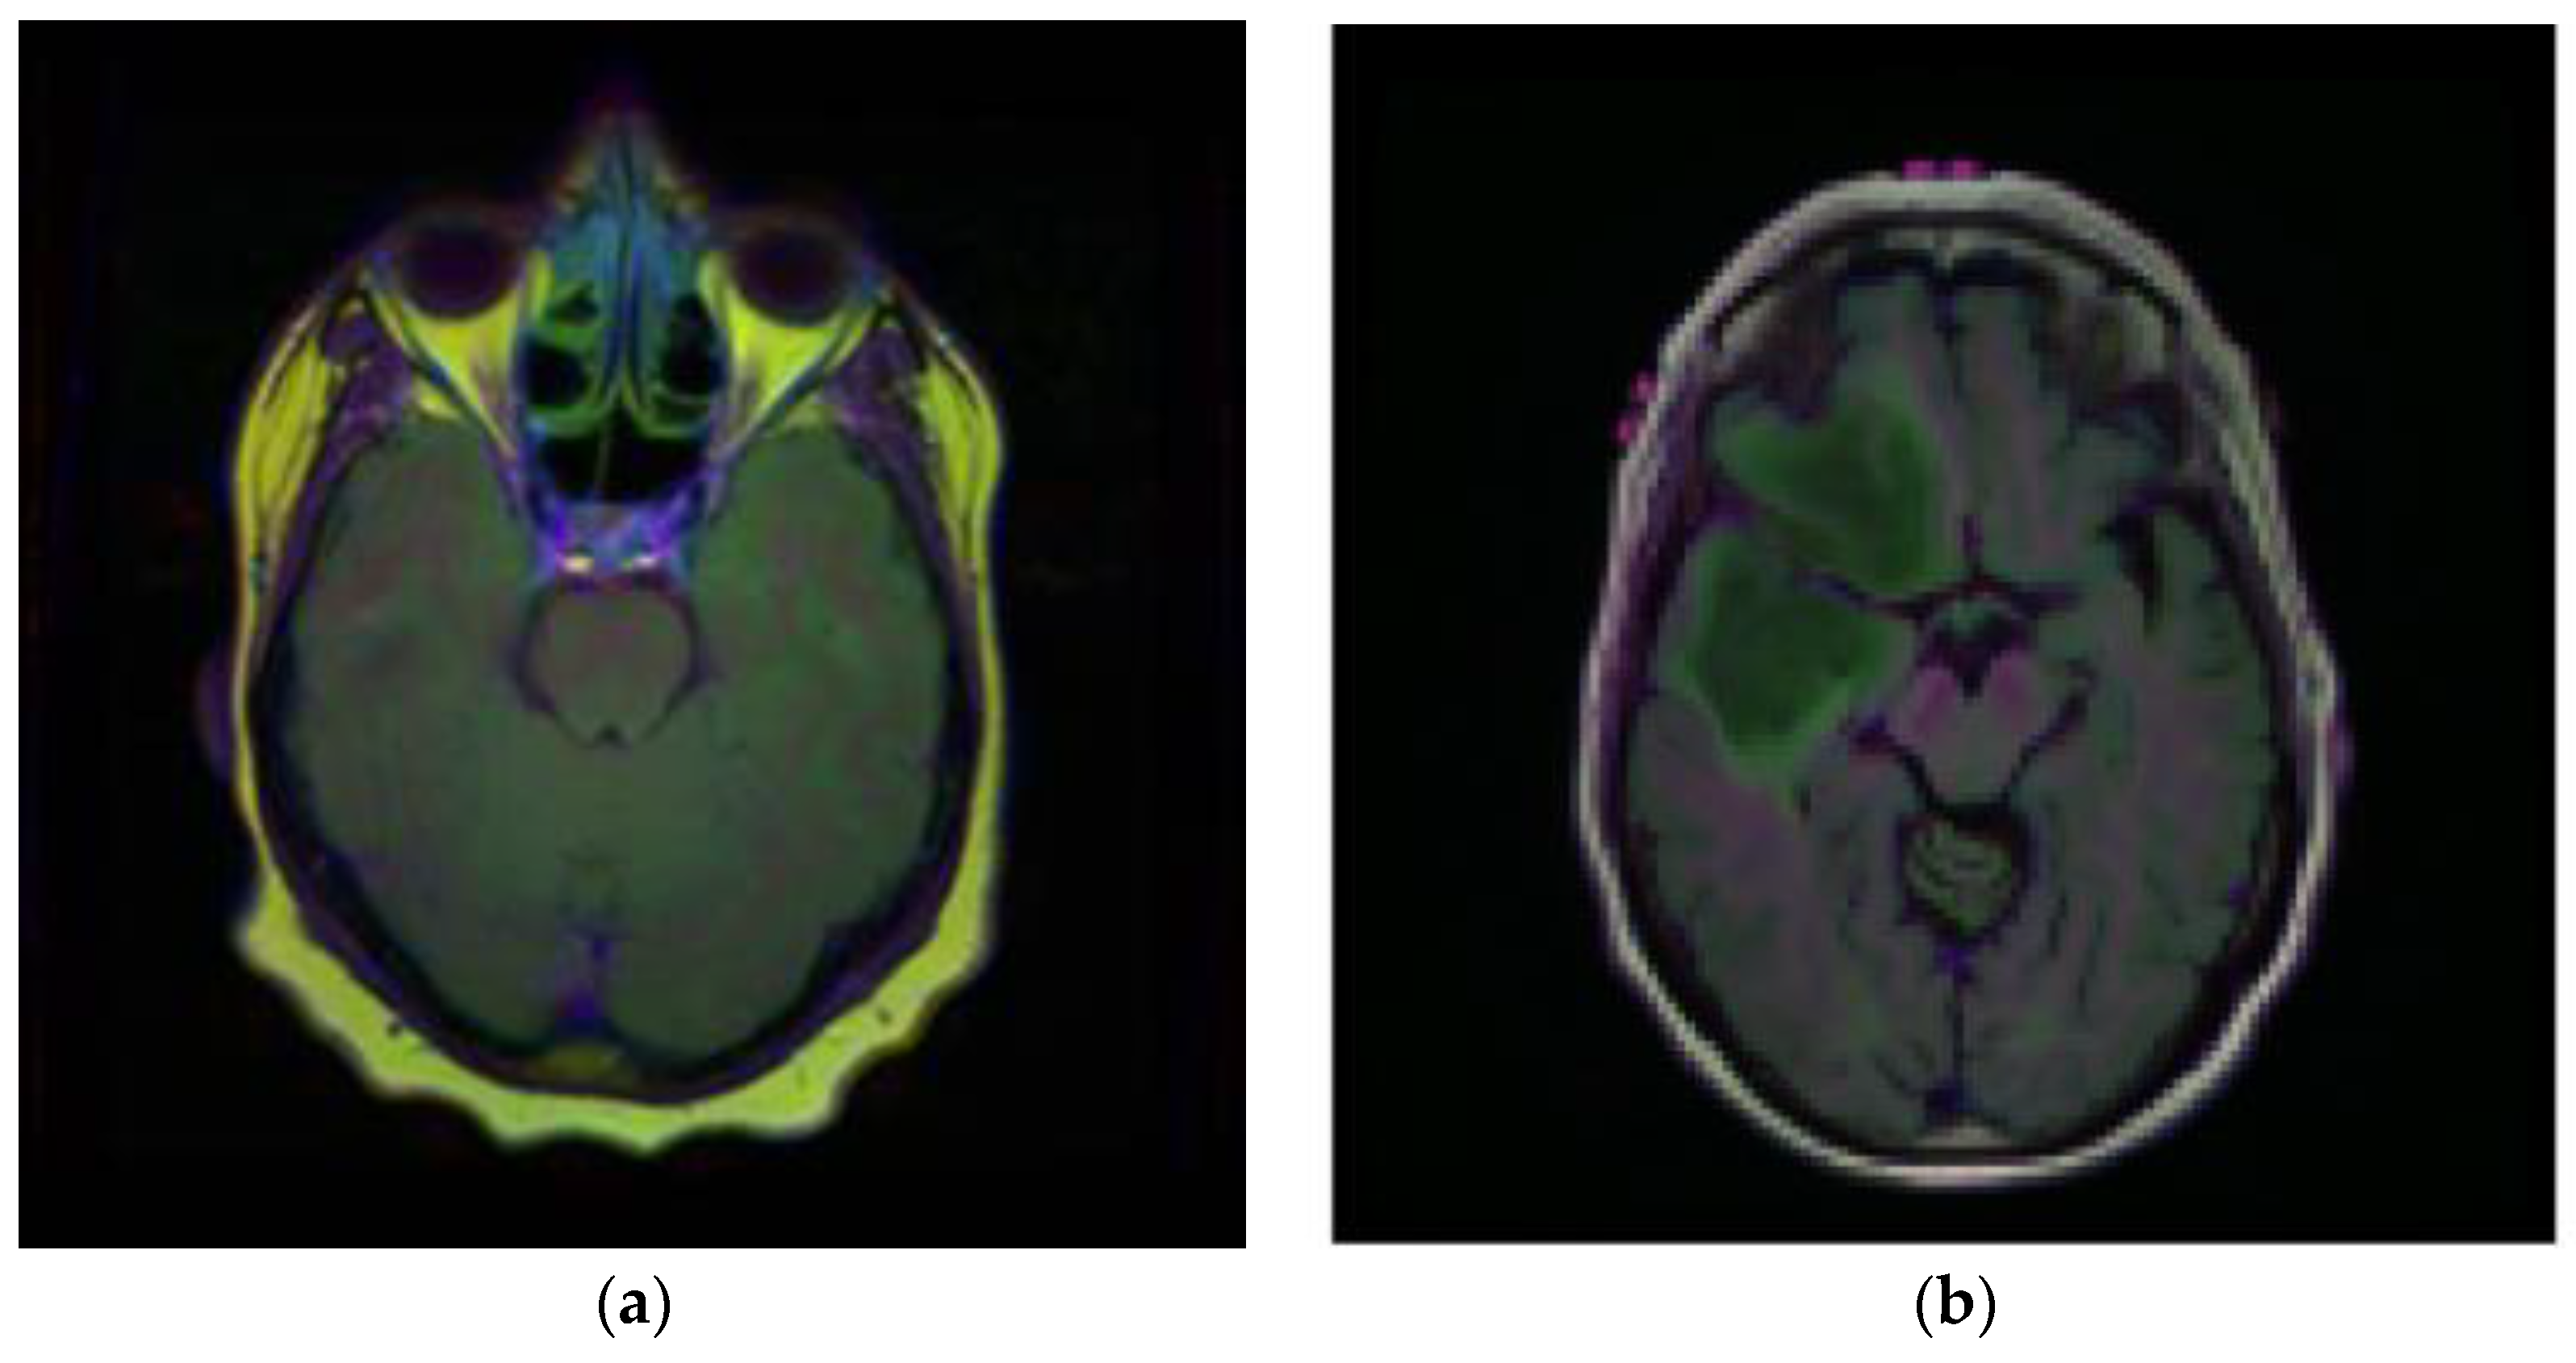

Brain MRI scans from 110 patients with 3929 brain MRI images are included in the dataset using FLAIR abnormalities. Out of the total 3929 dataset images, 90% of the data are used for training and 10% are used for testing. After that, out of the 90% training data, 15% are used for the validation set. Figure 2 illustrates the brain MRI images taken from Kaggle [28,29]. Figure 2a displays the normal image and Figure 2b displays the tumor image of the brain in which two tumor regions are shown with a break in between. It is difficult to segment this break region in the tumor part. The proposed methodology shown in Figure 3 is also segmenting this break part accurately.

Figure 2.

Samples of Brain MRI Images (a) Normal Image, (b) Tumor Image.